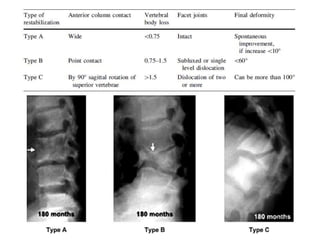

Risk factors for severe progression

• Age below 10 years.

• Vertebral body loss of more than 1–1.5

• A pre-treatment deformity angle of greater

than 30 deg, especially in children.

• Cervical thoracic and thoracolumbar

junctional lesions.

• The presence of ‘spine-at-risk’ radiological

signs.